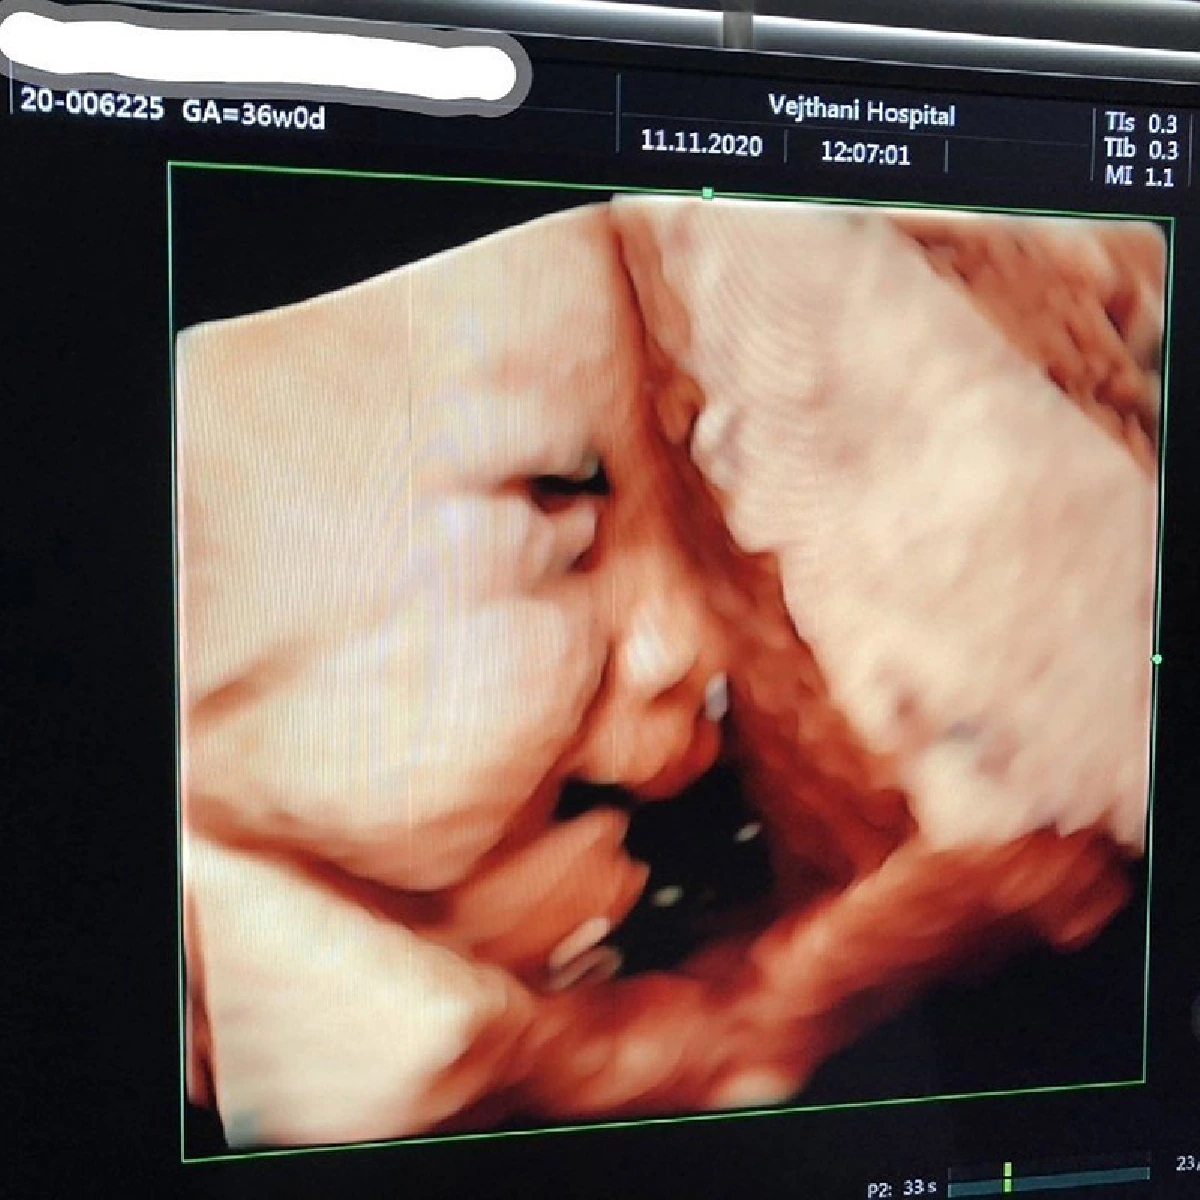

ล่าสุด หนุ่มต๊ะ บอยสเก๊าท์ ได้ออกมาโพสต์ภาพอัลตราซาวด์ลูกน้อยในท้องของภรรยา เผยโฉมเจ้าตัวน้อยครั้งแรกแบบชัดๆ พร้อมกับเล่าให้ฟังผ่านอินสตาแกรมว่า....

"36 Weeks วันนี้ เริ่มต้นที่คุณอาหมอภูมิพร บอกว่า "วันนี้ อาจจะเห็นหน้าน้องลำบากนิดนึงนะ เพราะว่าน้องกลับหัวแล้ว จะเห็นยากกว่าเดิม" พ่อกับแม่ก็ทำใจละ เพราะที่ผ่านมาคุณลูกก็ไม่ค่อยให้ความร่วมมือเท่าไหร่อยู่แล้ว แต่ที่ไหนได้ล่ะ วันนี้ คุณลูกสาวมาเต็มครับ โชว์พลังให้คุณอาหมอและคุณพ่อคุณแม่ดูซะเลย

คุณอาหมอบอกว่า สุขภาพแข็งแรงมาก น้ำหนักอาจจะน้อยกว่าเกณฑ์นิดหน่อยแต่ไม่มาก รอยหยักสมองเห็นชัด หัวใจดี ตาสองชั้นชัดมาก ออกซิเจนดี ทุกอย่างดีสมบูรณ์มาก

วันนี้ ลืมตา อ้าปากหาว ดูดนิ้วมือ แถมมีท่ากีฟมีไฟว์ให้พ่อกะแม่ด้วยนะ อีกไม่นานก็จะได้ออกมาโดนฟัดแล้ว พี่ป้าน้าอาที่รัก เป็นกำลังใจให้ครอบครัวเราด้วยนะครับ #รักใสๆหัวใจ3ดวงTBP #หลงลูก"